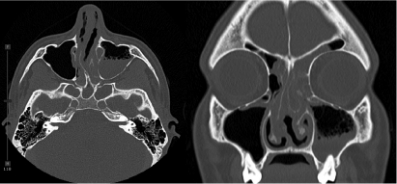

Scans